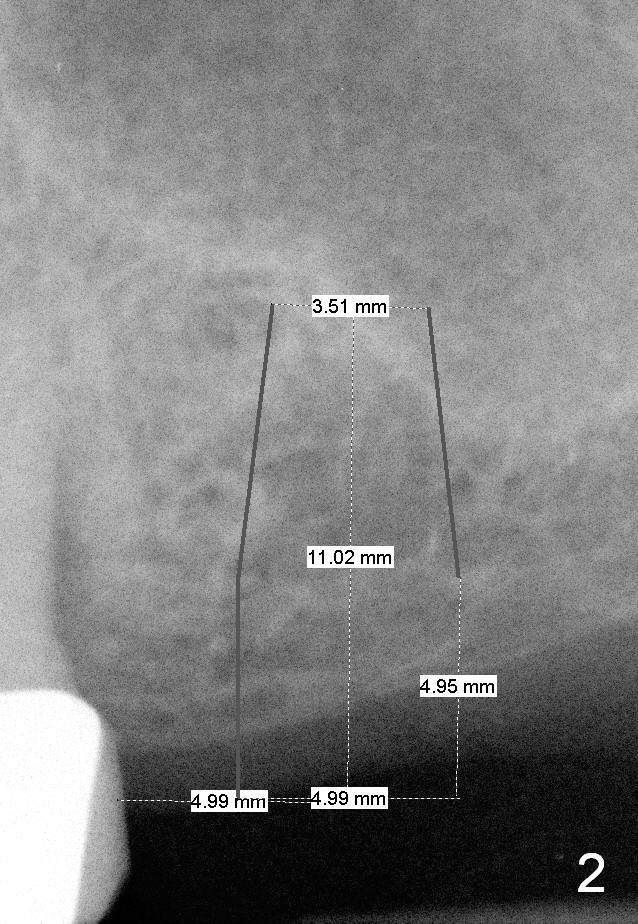

Mrs. Goh (71 years old) has lost 4 upper molars (Fig.1,6). The 1st sign of overload is increased periodontal space around the tooth #13 (Fig.1 *). The best way to tackle the overload is to place 4 implants. The 1st step is for the site of #14 (Fig.2: design; Fig.3: 4.5x11 mm tap; Fig.4: 5x11 mm implant). The 2nd sign of overload is repeated dislodgement of the implant supported crown. The 3rd sign of overload is bone loss around the implant 6 months post cementation (Fig.5 *). The 4th sign of overload is subgingival crown fracture of the tooth #5 (Fig.6).